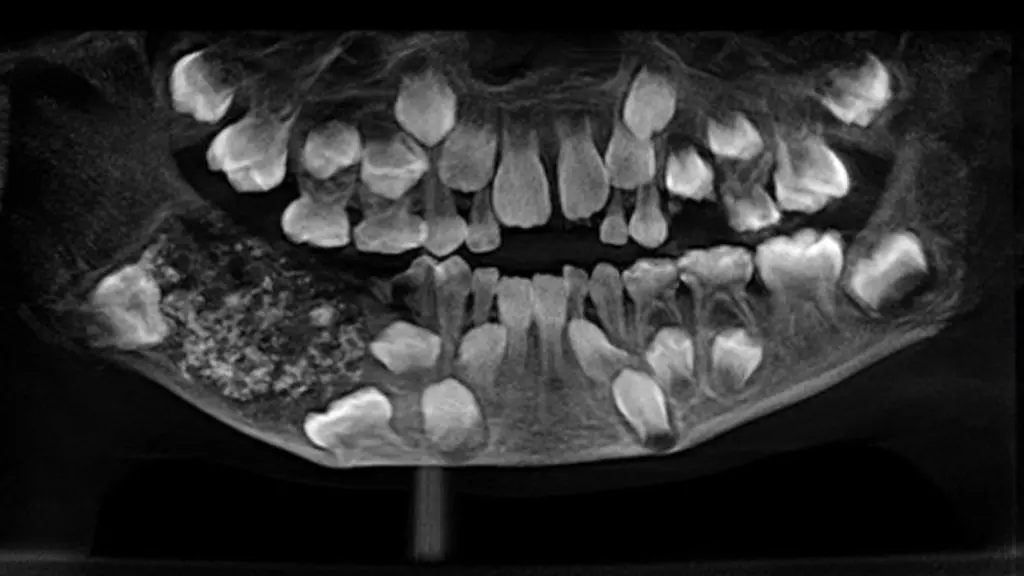

Eine ungewöhnlich große Zahl an Zähnen haben Ärzte im Südosten Indiens eigenen Angaben zufolge aus dem Kiefer eines Jungen herausoperiert. "Wir haben 526 Zähne in der Größenordnung von 0,1 Millimeter bis 15 Millimeter entfernt", sagte Pratibha Ramani, Chefin der Fachabteilung im Krankenhaus Saveetha Dental College and Hospital in Chennai. Alle Zähne hätten Wurzel, Krone sowie Zahnschmelz gehabt.

Ramani zufolge ist dies der bisher größte dokumentierte Fund von Zähnen im Mund eines Menschen. Der Siebenjährige habe zuvor über Kieferschmerzen und Schwellungen geklagt, ohne dass die im rechten Unterkiefer versteckten und nicht sichtbaren Zähne entdeckt worden seien, sagte Ramani weiter. Demnach litt er an einem sogenannten Odontom, einer gutartigen Geschwulst, die viele rudimentäre Zähne enthalten kann. Ungewöhnlich ist jedoch die Zahl.

2014 waren einem Teenager im westindischen Mumbai nach Angaben des Krankenhauses 232 Zähne entfernt worden. Röntgenbilder des Krankenhauses in Chennai zeigen eine Ansammlung von Zähnen. Der Junge habe nach dem Eingriff nun eine "gesunde Anzahl von 21 Zähnen" und sei drei Tage nach der Operation entlassen worden.